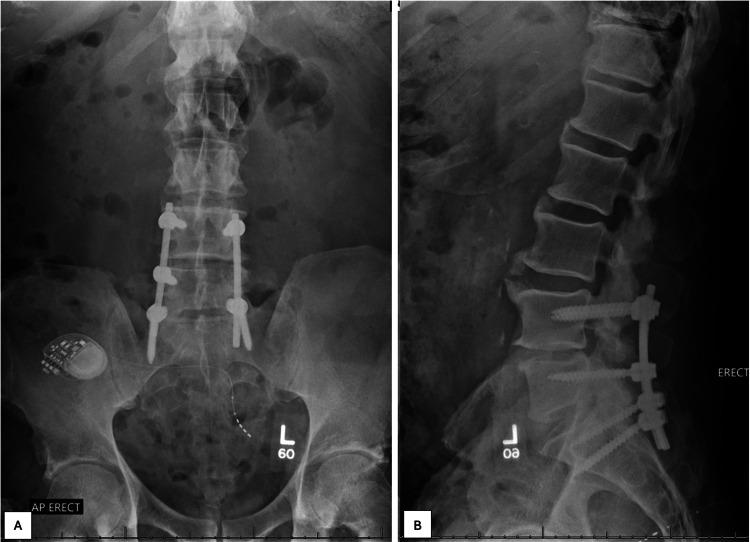

在本报告中,我们介绍了一名65岁前列腺癌病史患者,其存在一个逐渐增大的、退行性的、海绵状/椎体内髓核突出,也称为“许莫氏结节”。该患者最初因涉及L4和L5椎体的溶骨性病变来我们的骨肿瘤门诊评估。他大约在四年前被诊断为前列腺癌,此前接受过前列腺切除术。在评估神经源性间歇性跛行症状期间,计算机断层扫描(CT)显示L5椎体有一个低密度病变,在焦磷酸锝核闪烁扫描和18氟氟脱氧葡萄糖正电子发射断层扫描-CT上,L5左侧摄取轻度增加。对该病变进行了CT引导下细针穿刺抽吸(FNA),未发现肿瘤性病变。他接受了L4-L5显微镜下单侧椎板切开术及双侧减压。然而,他的神经源性间歇性跛行逐渐复发,于是他找脊柱外科医生进行进一步评估。腰椎重复CT显示,侵蚀性L5病变明显扩大,边界不清,L4左侧还有一个低密度侵蚀性病变。患者再次接受FNA,并在外部机构进行了CT引导下病变的粗针活检,结果未得到诊断性标本。在与患者进行广泛讨论后,最终决定通过左侧经椎弓根入路对L5病变进行开放性活检并部分切除L5椎体,同时进行L4-S1减压和后路外侧脊柱内固定融合术。手术的主要目的是从病变中取出材料,直接观察病变,并获取足够的组织进行组织病理学分析。基于这些术中发现及随后的最终组织病理学评估,该病变最终被确诊为一个大的、侵袭性的、海绵状/椎体内髓核突出。虽然将非肿瘤性病变,如许莫氏结节,与骨转移性脊柱疾病区分开来可能很困难,但这对于有恶性肿瘤病史患者的恰当管理至关重要。